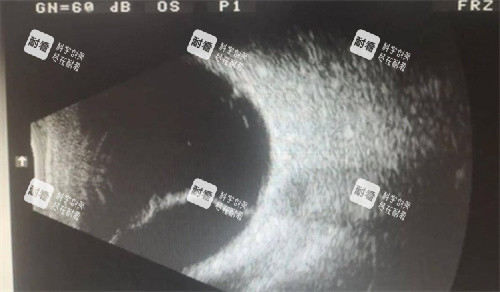

术前检查费

术前需要进行一系列的检查,如眼部超声、眼底照相、眼压测量等,以确定视网膜脱落的情况和患者的眼部整体状况。这些检查费用大约在 1000 - 2000 元左右。